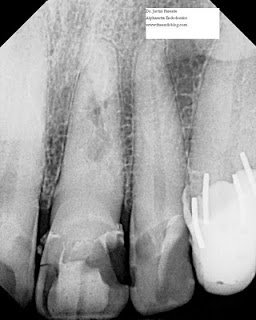

This next case is similar, although a little less conventional. As you can see in the preoperative radiograph, the root is severely dilacerated. While certainly it is possible to perform root canal therapy on this type of root (see my previous post for an arguably more challenging S curve), the difficulty level is unquestionably high. This treatment plan not only reduces the risk of instrument separation, but also saves the patient time and money, and the operator from fatigue.

The key here is that this was an asymptomatic carious pulp exposure. In the case of symptoms of irreversible pulpitis, it is generally thought that an MTA pulpotomy is a more risky procedure. It is certainly contraindicated in cases with symptomatic apical periodontitis (although I have had success direct pulp capping an immature tooth with apical periodontitis).